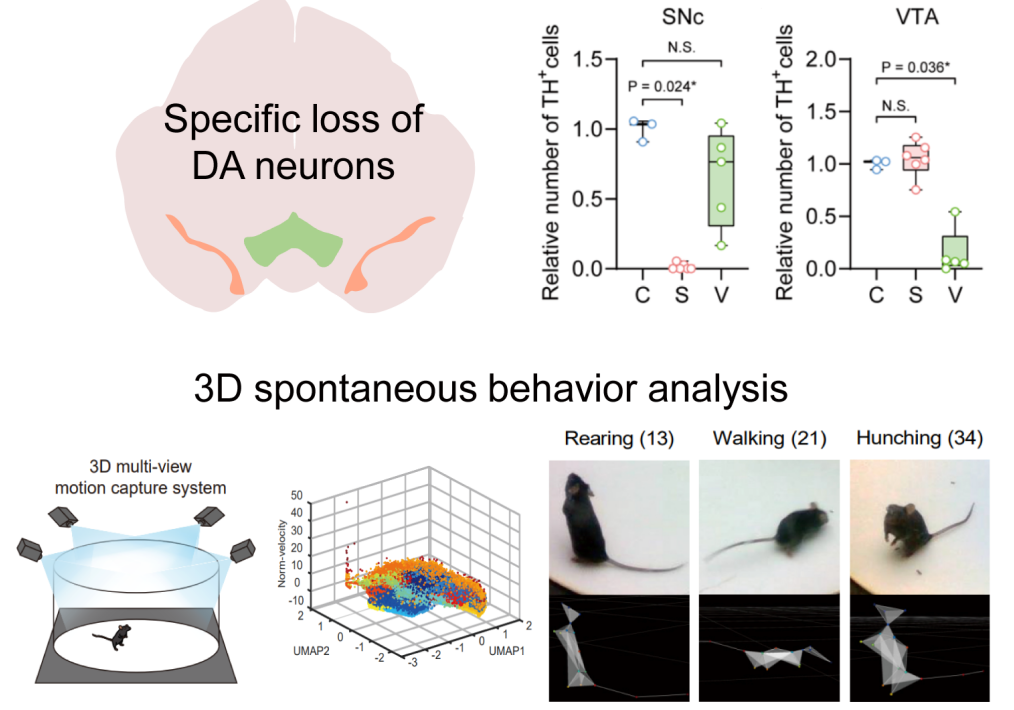

May 23, 2025Subtle Movement Shifts May Enable Earlier Parkinson's DetectionThese findings highlight the significance of rearing behavior and behavioral lateralization as potential behavioral markers for tracking the progression of Parkinson's disease. Midbrain dopamine (DA) neurons, located in the substantia nigra pars compacta (SNc) and the ventral tegmental area (VTA), are essential for regulating movement, emotion, and reward processing. Dysf...